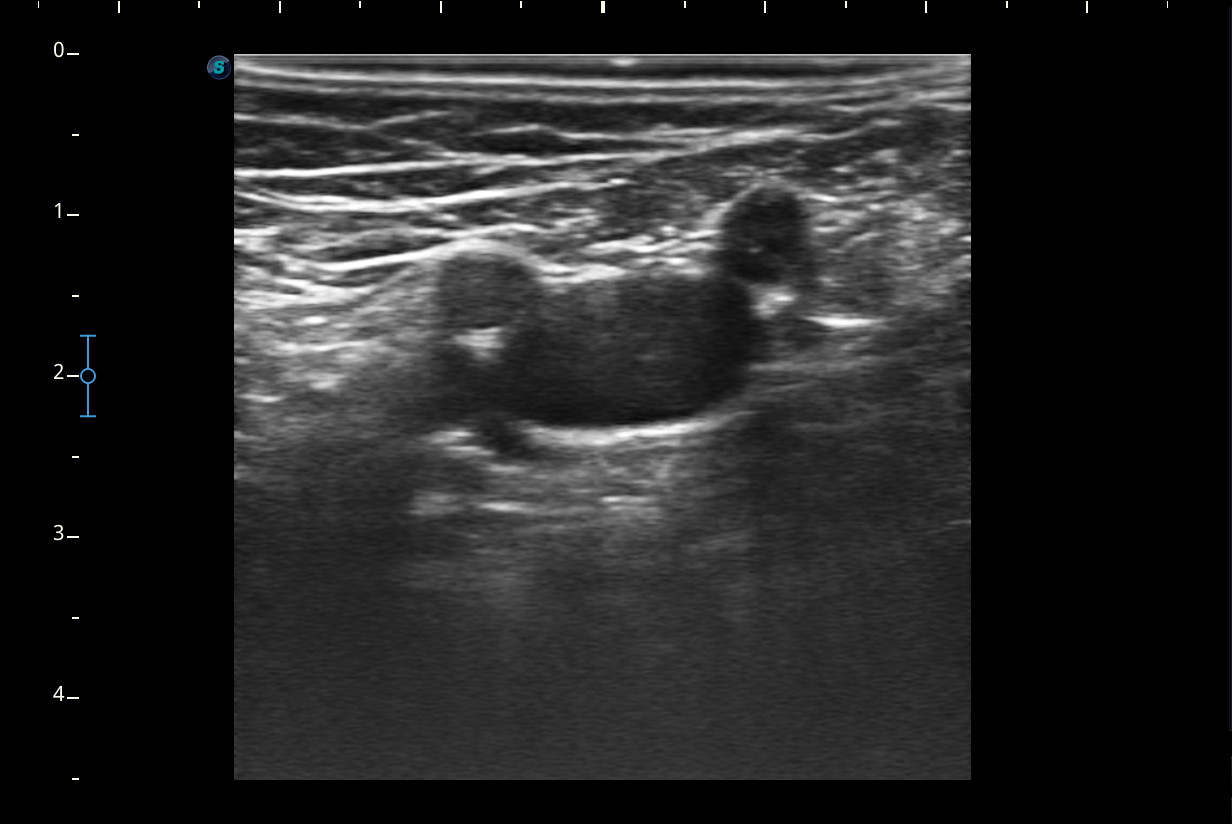

Se realiza ecografía del Miembro inferior derecho.

A nivel del hueco poplíteo se visualiza presencia de trombosis de la vena poplítea, no así en localizaciones proximales.